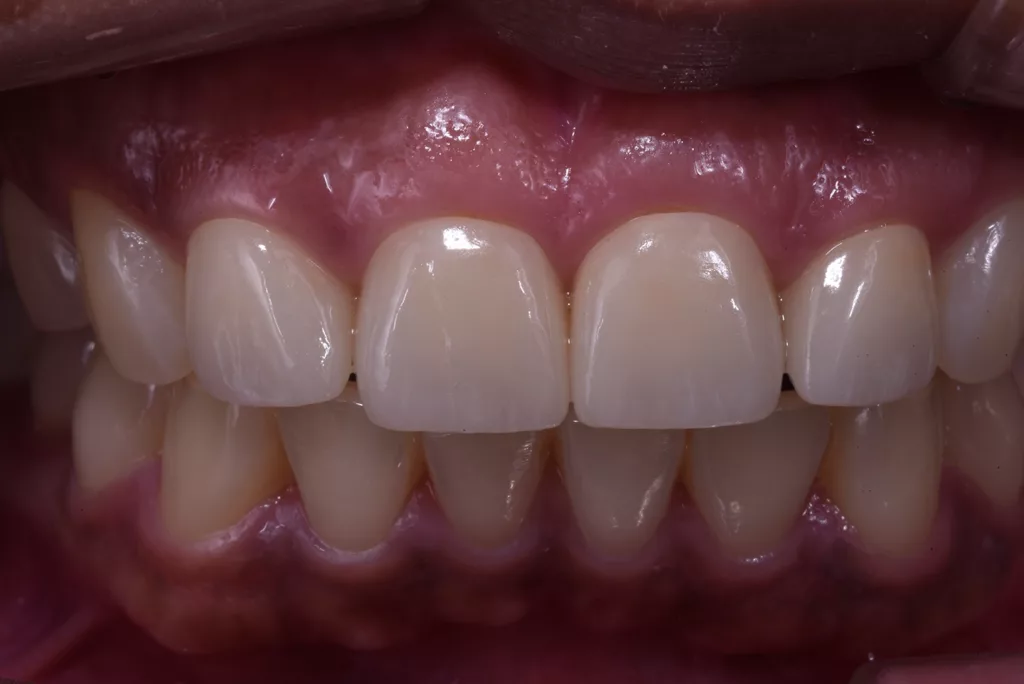

Die fertigen Kronen nahmen die natürliche Zahnfarbe auf und überzeugten durch eine außergewöhnliche Transparenz. Obwohl die Präparationsrichtlinien für Frontzähne eine Kronendicke von 0,8 mm vorsehen, erfolgte aufgrund der Vitalität der Zähne eine möglichst geringe Präparation. Zwar erschienen die beiden mittleren Schneidezähne zunächst etwas kürzer, aber tatsächlich wurde die Länge der Kronen unter Berücksichtigung der aufgezeichneten Frontzahnführung der Patientin angemessen bestimmt. Durch diese Vorgehensweise lässt sich sicherstellen, dass die Kronen langlebig und geschützt sind (Abb. 64 bis 67).